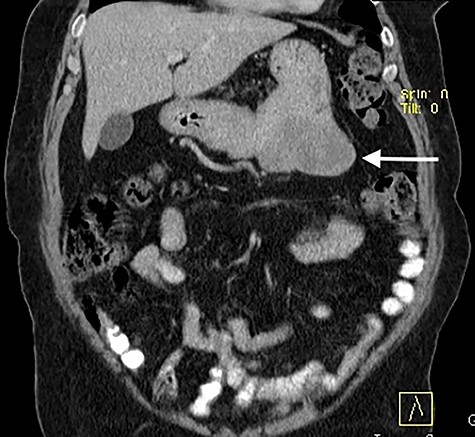

Computed tomography contrast-enhanced scan: predominantly exophytic neoplasm growing from gastric greater curvature (arrow) with 97 × 77 × 57 mm; no signs of metastatic or locally advanced disease were found.

Presenting an initial clinical picture of epigastric pain and nonspecific dyspeptic symptoms, the patient underwent upper gastrointestinal endoscopy (Fig. 1) where a subepithelial lesion was found, mandating further investigation. Endoscopic ultrasonography (Fig. 2) arose suspicion of GIST and computed tomography scan (Fig. 3) revealed an exophytic lesion with 97 × 77 × 57 mm rising from the gastric greater curvature, with no signs of metastatic or locally advanced disease.